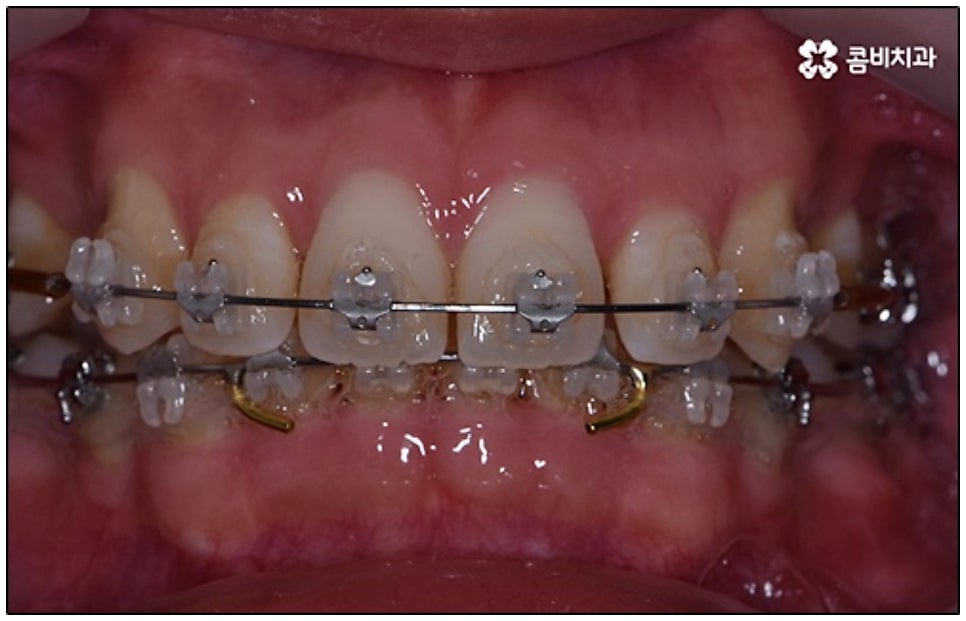

말씀드린 것과 같은 다양한 이점들이 있기 때문에 현재 본원의 교정 환자분들은 대부분 클리피씨교정 장치를 이용하여 치료를 진행하고 있습니다. 사진 역시 돌출입 교정을 위해 발치 후 클리피씨교정 장치를 이용하신 환자분의 케이스인데 시간이 지날수록 점차 앞니가 자연스럽게 들어가고 위아래 교합이 정확하게 맞아가는 것을 확인하실 수 있을 거예요.